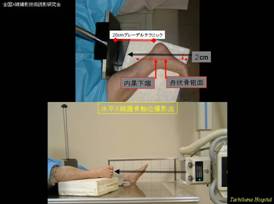

② 患者さんに優しい踵骨軸位水平X線撮影法(踵骨側面撮影後にそのままの体位で)

体位・入射点:踵骨側面撮影の後、そのままの状態から写真のような体位を作る。

撮影距離は100cm以上とし、踵骨―フィルム間に20cm程度のグレーデルテクニックを用いる。撮影条件は管電圧60kVくらいで適切な濃度が得られる照射量とする。

入射点は、内果下端と舟状骨粗面を触知しラインを作り、そのラインに平行で、2cm足底寄りに直交入射する。